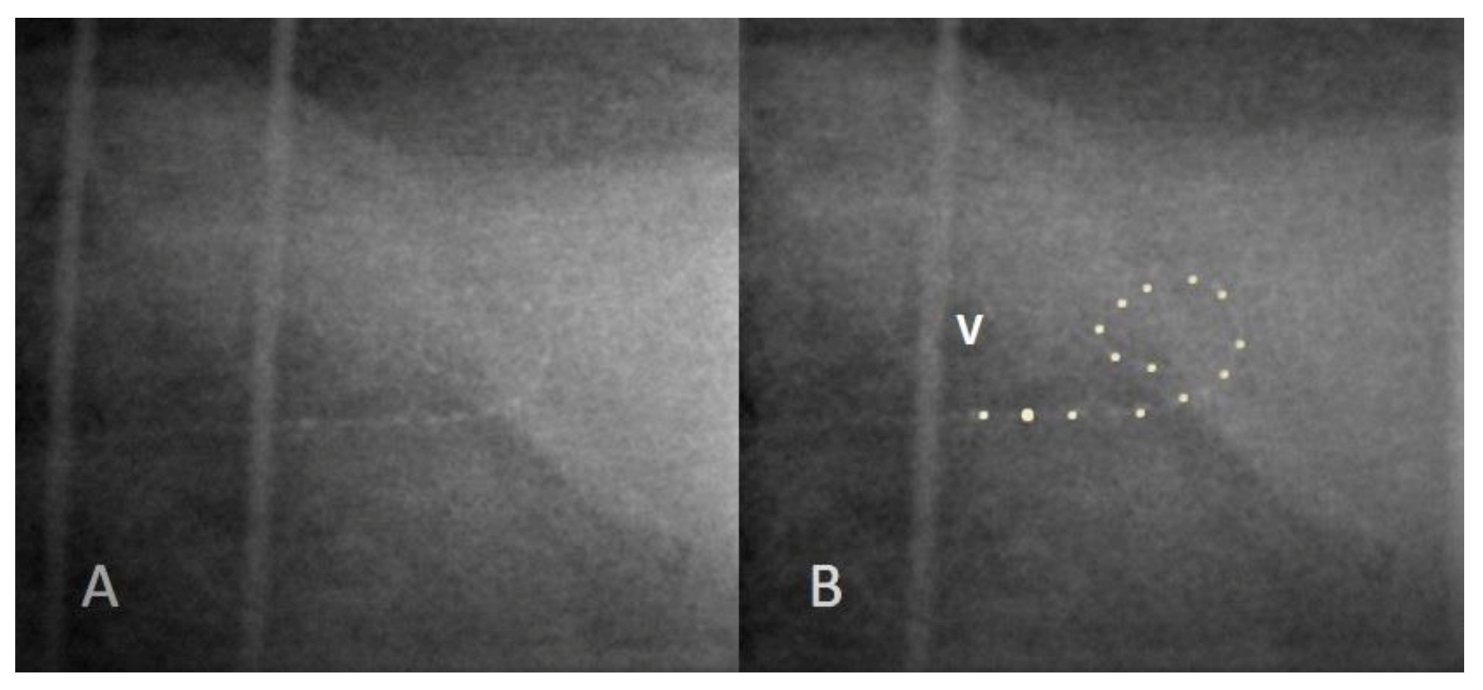

3.3. Case 3: Extracochlear Electrode Array Malposition